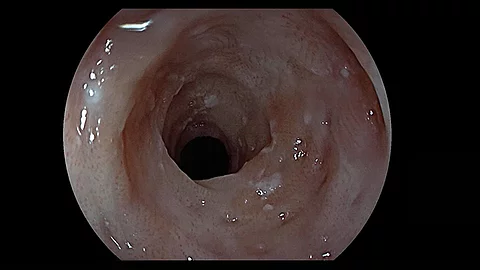

Endoskopisches LehrvideoGezielte Biopsieentnahme im Ösophagus

Wie entnimmt man im Ösophagus am besten gezielte Biopsien und welche Schritte sind dabei entscheidend? Genau das zeigt Ihnen PD Dr. Jochen Weigt vom Universitätsklinikum Magdeburg im neuen Video.